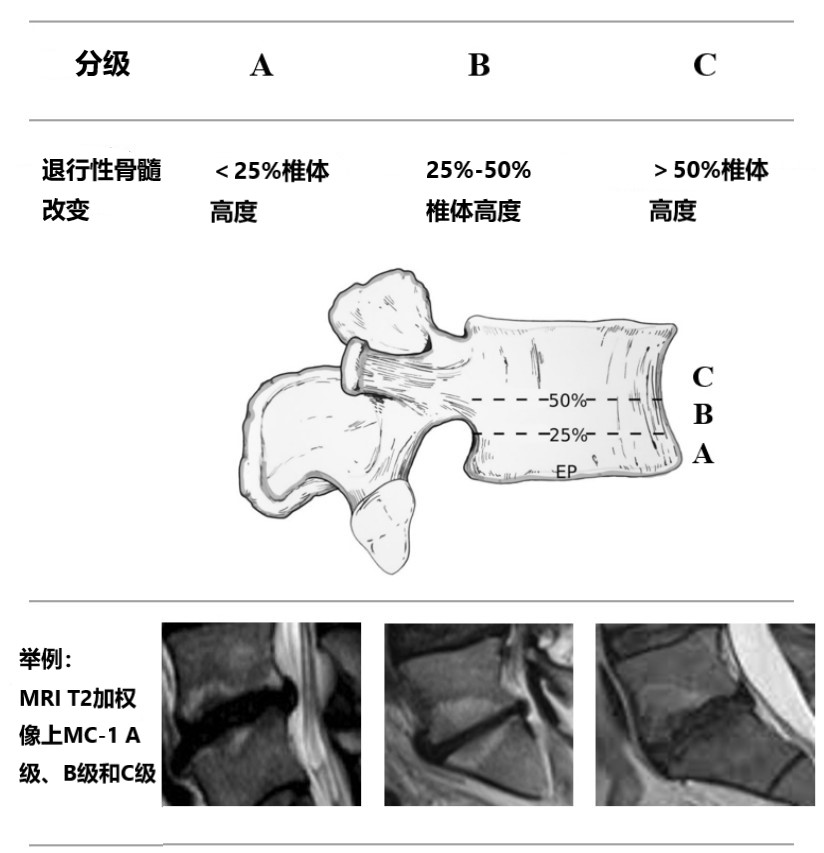

最近,Udby 等依据椎体受累程度,提出了 Modic 改变临床分级:

类似于椎间盘退变可使用 Pfirrmann 分类对其严重程度进行分级,Modic 改变的描述也需要同时考虑骨髓改变的分型和分级。

如果同一功能单元内存在不同/混合型 Modic 改变,则应描述最具临床意义的 Modic 改变(首先 Ⅰ 型,其次 Ⅱ 型,最后是 Ⅲ 型)。

而最严重的分级,根据椎体内 Modic 改变垂直范围最大的矢状切面,应使用 C 级 > B 级 > A 级,以清楚地描述功能单元内最具有临床相关性的变化。